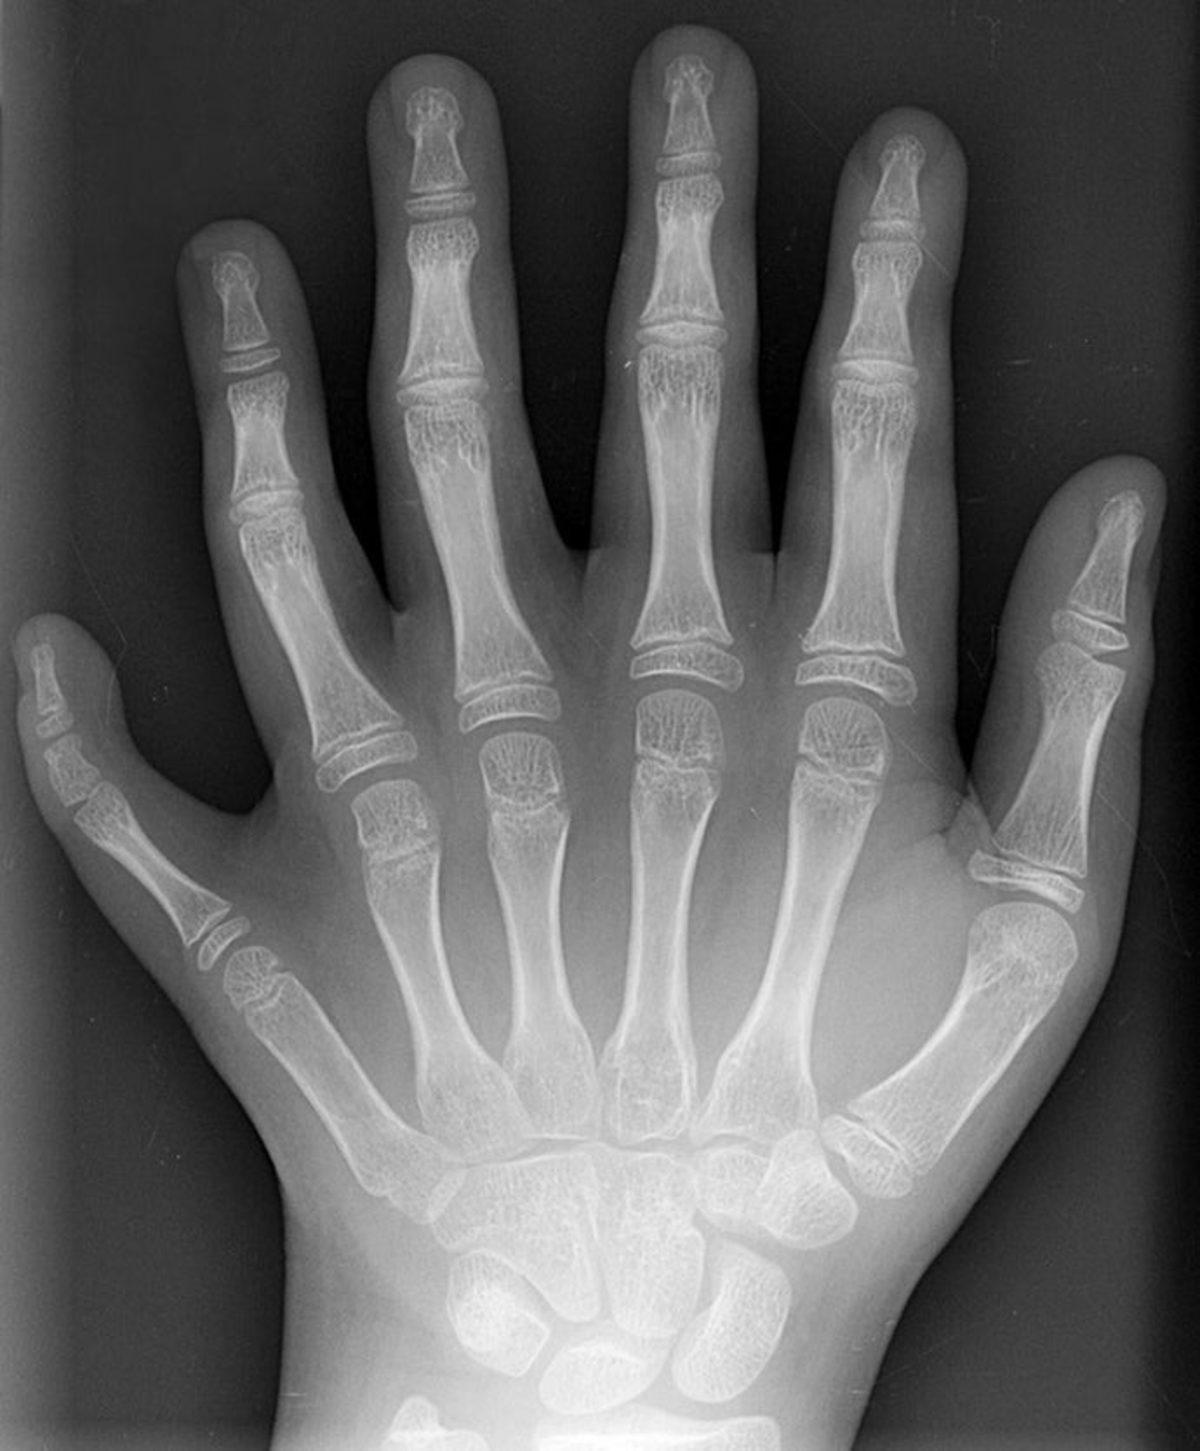

Nature Communications’da yayımlanan bir makalede, altı parmaklı insanların yetenekleri incelendi. Bu durum, kabaca her 500 kişiden birinde görülüyor. Bu durum genel olarak altıncı parmağın işlevsiz olacağı inanışı nedeniyle fazla parmağın alınmasıyla sonuçlanıyor. Altıncı parmağı alınmamış bir kadın ve kadının yine altı parmaklı oğluyla yapılan çalışmalar ise bu bedensel farkların kötü bir şey olmadığını, aksine işlevli olabildiklerini gösterdi.

İlk olarak, altıncı parmakların hem sinirsel hem de kas sistemi açısından komşularına bir engel çıkarmıyor. Kendi özel sistemlerine sahip. Yani diğer parmaklarda işlevsel açıdan bir sıkıntı oluşturmuyor.

Araştırmacılar, her iki örnekte de beynin motor korteksinde bu parmaklara ait ayrı bölgeler keşfetti. Ayrıca bu kişiler, klavyeye bakmadan yazmak gibi testlerde de altıncı parmaklarını göremedikleri durumda bile parmaklarının yerini bildiklerini gösterdi.